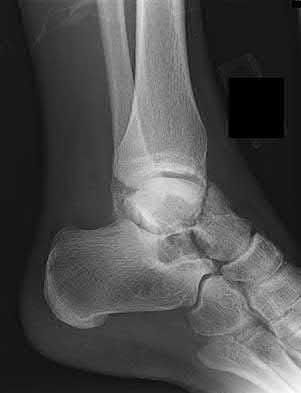

4. # After undergoing the treatment seen in Figure A, when should a patient be expected to safely operate the brakes of an automobile?

Figure A shows a patient after an open reduction and internal fixation of a bimalleolar ankle fracture.

Egol et al showed that by nine weeks, the total braking time of patients who had undergone fixation of a displaced right ankle fracture returns to the normal, baseline value.

Egol et al, also found that appropriate braking time returns at a point 6 weeks after initiation of weightbearing after treatment of lower extremity long bone and periarticular fractures, as examined with a driving simulator. No differences were seen in return of braking time between periarticular fractures and long bone injuries.